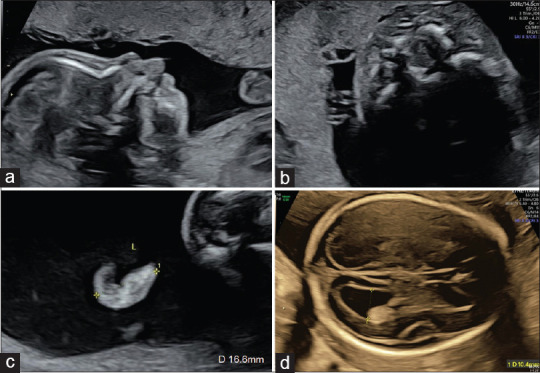

Monogenic Syndromes: The Need for Clinical Vigilance in Fetuses with Pierre Robin Sequence in the Era of Noninvasive Prenatal Screening.